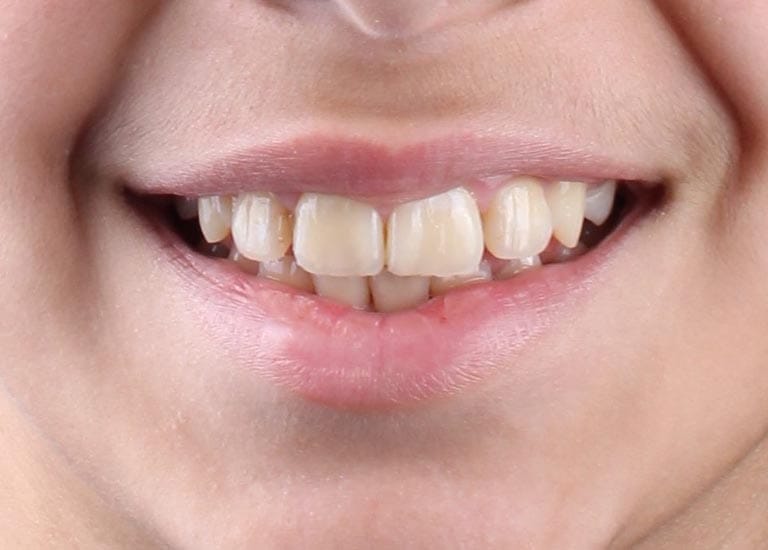

BEFORE

This young woman suffered from an upper jaw stenosis, crowded teeth, and the absence of one of the upper molars.

She was treated with Daimon braces (an orthodontic device that doesn’t require rubber to fix the archwires, which reduces friction and speeds up treatment).

At the end of the treatment, we were able to see a clear expansion in her upper jaw, her teeth were aligned beautifully, and the gap resulting from the absence of the molar was closed orthodontically.